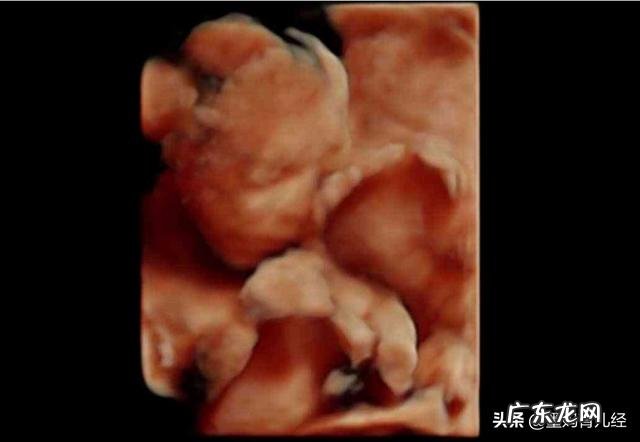

(20周 , 胎儿的三维彩超情况)

怀孕20周胎宝宝已经像一个甜瓜 , 那么大了 , 宝宝的身长约25cm , 头臀长约16cm , 体重约320g , 生长趋于稳定 。

孕20周的时候宝宝的胳膊和腿与身体的其他部分成比例了 , 头皮上的头发开始长出 , 眉毛也开始形成 , 皮肤暗红 , 全身覆盖毳毛 , 胎宝宝的身体表面也会覆盖一层白白的脂肪 , 也就是我们所说的胎脂 。

孕20周的时候 , 宝宝也学会了很多本领 , 宝宝的肌肉发育的比较快 , 体力也增强了许多 , 小手小脚都能在羊水中自由活动了 , 子宫留给宝宝的空间足够大 , 所以宝宝此时可以在妈妈的肚子里扭动、翻身、踢打 , 甚至偶尔翻跟头 , 除此之外还会吮吸手指、打嗝、揉眼睛……此时大部分妈妈也已经可以感受到宝宝的这些动作了 , 即胎动 , 不过此时妈妈们所能感受的胎动仍然是比较轻微的 。